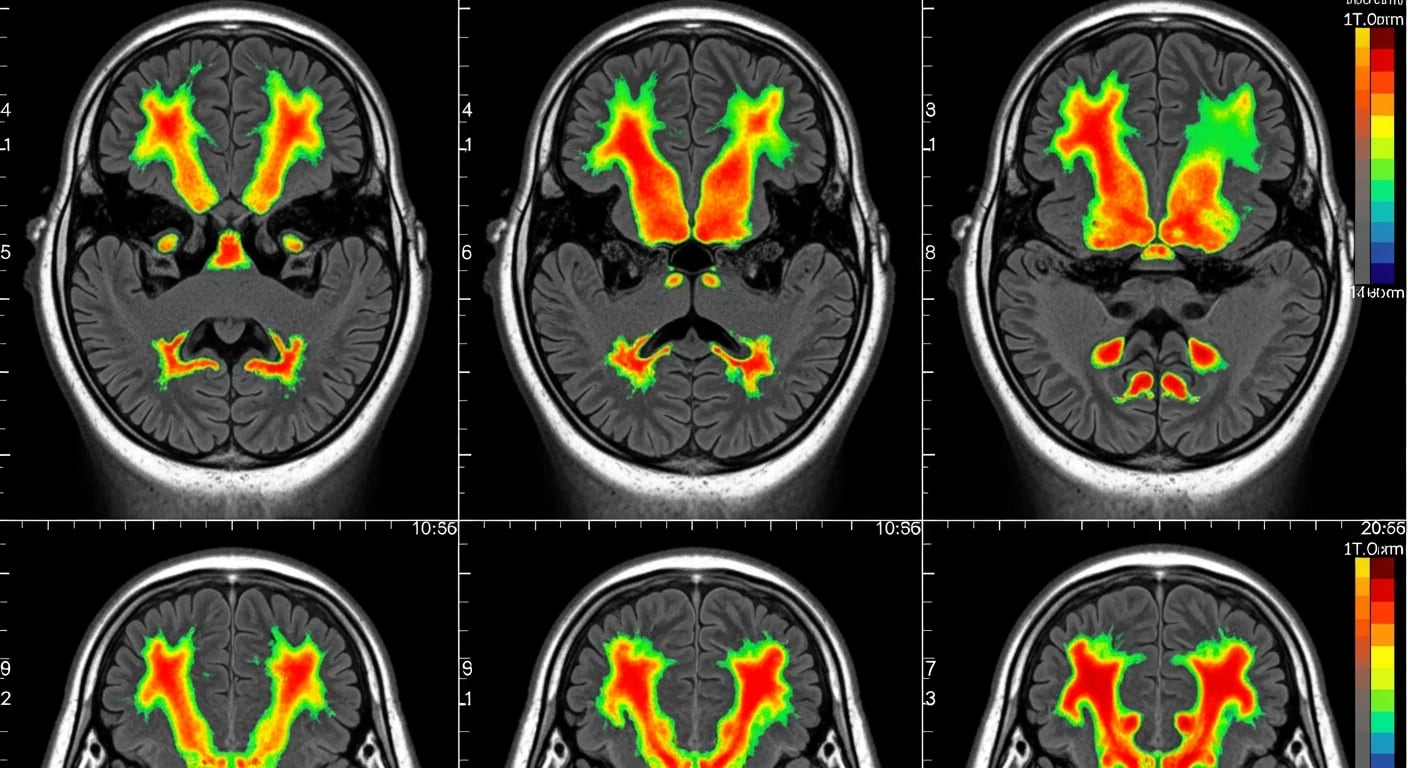

El estudio, liderado por Matthias Grabenhorst, se basó en experimentos con 13 adultos en laboratorios de Alemania y Estados Unidos, quienes respondieron a señales visuales y auditivas que podían aparecer en cualquier momento dentro de un intervalo de hasta tres segundos. Se recopilaron más de 52.000 tiempos de reacción, lo que permitió analizar la manera en que el cerebro ajusta sus estimaciones de probabilidad en tiempo real ante estímulos cambiantes.

El análisis reveló que el cerebro utiliza un mismo sistema de anticipación tanto si el estímulo ocurre en una fracción de segundo como si tarda varios segundos en aparecer. Este hallazgo desafía teorías clásicas como la ley de Weber, que sostiene que la incertidumbre sobre la estimación temporal crece con el paso del tiempo. En cambio, los resultados publicados en PNAS muestran que la precisión depende sobre todo de la probabilidad que el cerebro atribuye a la ocurrencia de un evento: cuando esta es alta, el margen de error disminuye, incluso en intervalos largos.

Los modelos matemáticos empleados por el equipo investigador —como el “escalamiento temporal” y la “normalización divisiva”— explican cómo distintos grupos neuronales se activan en proporciones fijas, aunque cambie la duración del intervalo. Esta arquitectura permite mantener una precisión constante y flexible, y almacenar información sobre la probabilidad asociada a cada instante posible, facilitando la preparación motora antes de que ocurra el estímulo.